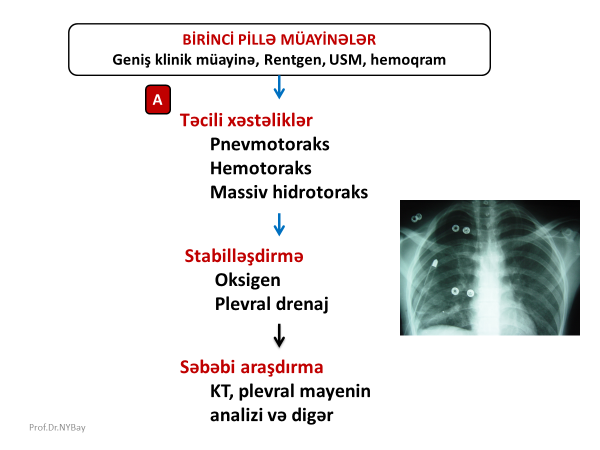

Şəkil 1. Birinci pillə müayinələrin nəticələri

Birinci pillə

Birinci pillə müayinələrdə məqsəd plevrada təcili cərrahi xəstəliyin olub-olmamasını, maye, kütlə və fistula kimi üzvi dəyişikliklərin olub-olmamasını müəyyənləşdirməkdir. Bunun üçün hərtərəfli klinik müayinə, hemoqram, Rentgen və USM edilir. Birinci pillə müayinələrdən bir neçə nəticə ortaya çıxa bilər (Şəkil 1):

- Təcili xəstəliklər

- Plevral maye

- Plevrada törəmə

- Döş divarında fistula

Təcili xəstəliklərdə diaqnostika

Plevranın təcili müdaxilə tələb edən xəstəliklərinə pnevmotoraks, hemotoraks və massiv plevral maye aiddir. İlkin klinik-görüntüləmə müayinələrində təcili xəstəliklər olarsa əvvəlcə xəstəni stabilləşdirmək, sonra səbəbi araşdırmaq lazımdır. Stabilləşdirmək üçün (tənəffüsü və qan dövranını bərpa etmək) oksigenoterapiya və plevral drenaj gərəkir. Səbəbin müəyyənləşdirilməsi üçün isə klinik məlumatlar, KT və plevral mayenin müayinəsi nəzərə alınır (Şəkil 2).

Şəkil 2. Plevranın təcili xəstəliklərində ümümi yanaşma